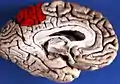

|  Medial surface of left cerebral hemisphere. (Precuneus visible at top left.) (Anterior to the right.) | |